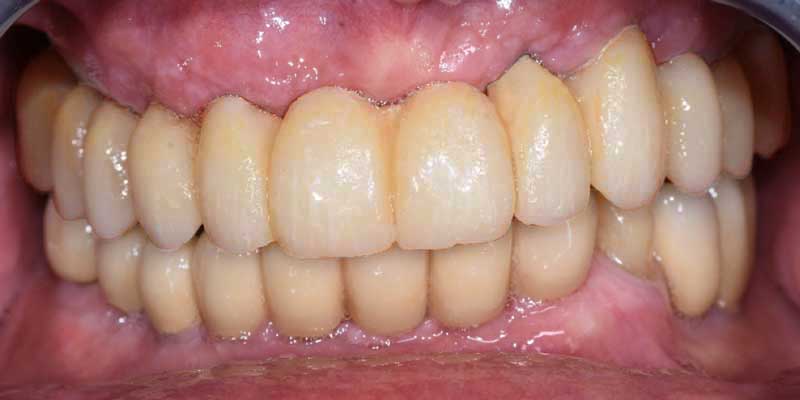

Subito dopo il posizionamento degli impianti, il dentista fissa una protesi, realizzata già in fase di progettazione e che testimonia la precisione della pianificazione. Questa permette al paziente di masticare subito dopo l’intervento. Questi denti provvisori sono progettati per essere funzionali e stabili.

Aspetto della nuova protesi dopo l’intervento

Durante i mesi successivi, in cui gli impianti si integrano all’osso (processo chiamato osteointegrazione), il paziente porta la protesi temporanea che verrà sostituita con quella definitiva solo quando gli impianti saranno completamente integrati (circa dopo 3 mesi).